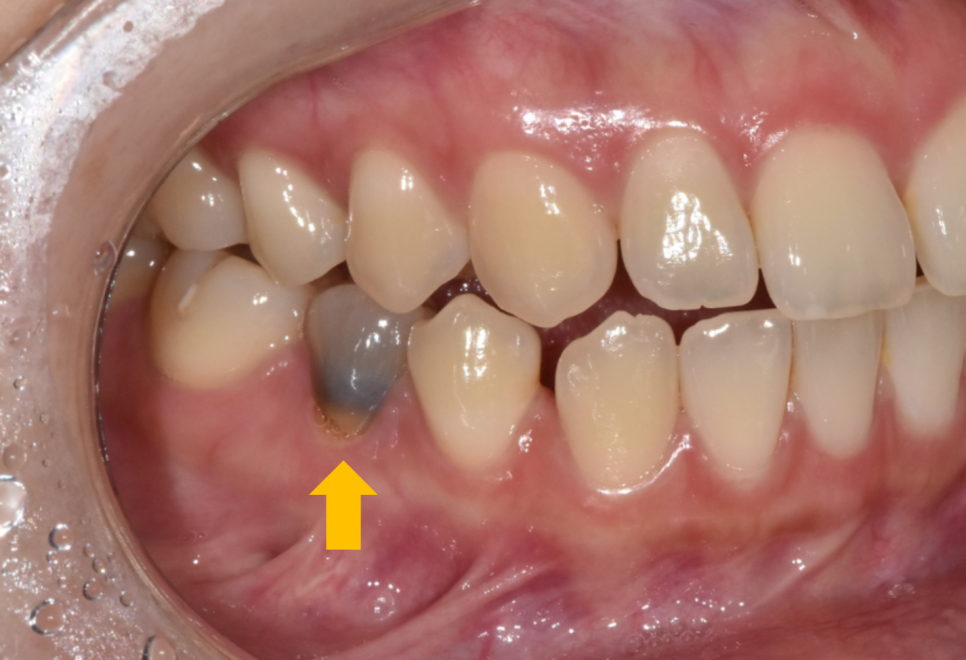

최근 진료실에 찾아오신 한 환자분 이야기입니다.

예전에 임신 중 치아가 너~무 아파

신경치료만 받고 방치해두셨답니다.

어느날부터 치아가 까맣게 변했는데...

말하거나 음식을 먹을 때마다

너무나 신경이 쓰인다고 하셨어요.

직접 눈으로 확인해보니

유달리 까만 치아가 눈에 너무나 잘 들어오네요~

주변 하얀 치아와 비교하여

대비되기도 하고요.